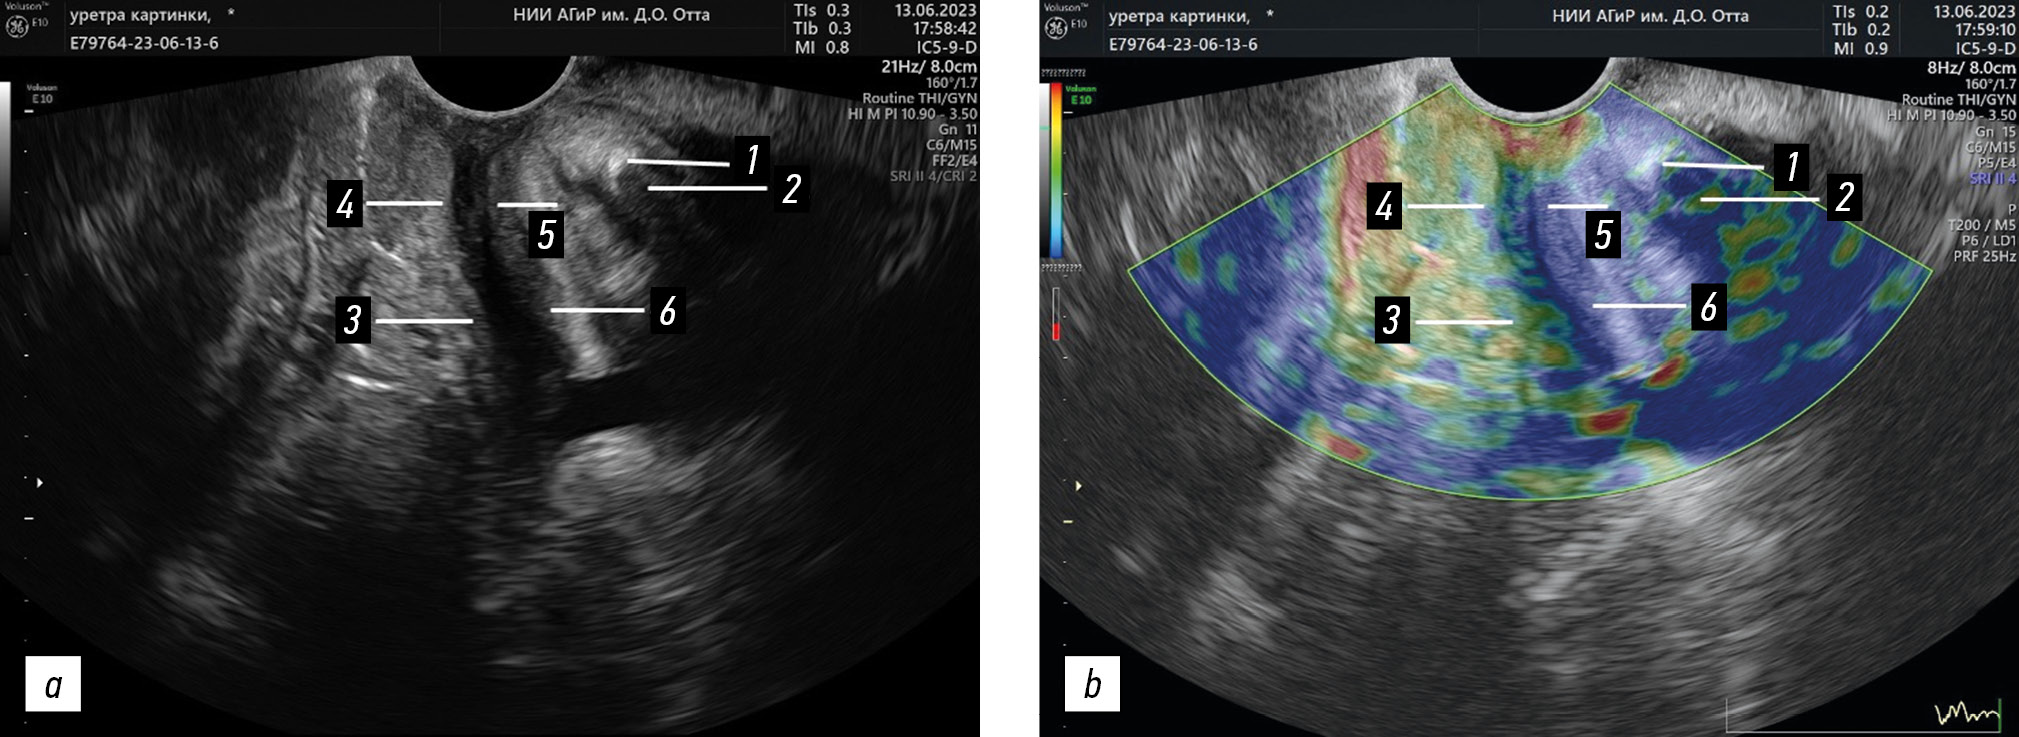

Рис. 2. Исследование уретровезикального сегмента трансперинеальным доступом с указанием исследуемых опорных структур уретры (использованы ультразвуковая система Voluson E10, мультичастотный трансвагинальный датчик RIC 5-9-D): a — 2D-эхограмма; b — эластограмма. 1 — лобковая кость; 2 — жировая ткань позадилобкового пространства (зона контроля); 3 — задняя стенка влагалища с лобково-шеечной фасцией рядом с задней стенкой проксимального отдела уретры (первая зона интереса); 4 — задняя стенка влагалища с лобково-шеечной фасцией рядом с задней стенкой среднего отдела уретры (вторая зона интереса); 5 — компрессор уретры и уретровлагалищный сфинктер, образующие рабдосфинктер (третья зона интереса); 6 — лобковопузырная мышца (четвертая зона интереса)

Fig. 2. Investigation of the ureterovesical junction of a patient using transperineal access, with the studied urethral supporting structures indicated (Voluson E10 ultrasound system; RIC 5-9-D transvaginal probe): a, 2D echogram; b, elastography. 1, pubic bone; 2, adipose tissue of the retropubic space (control area); 3, posterior vaginal wall with pubocervical fascia near the posterior wall of the proximal urethra (first area of interest); 4, posterior vaginal wall with pubocervical fascia next to the back wall of the middle part of the urethra (second area of interest); 5, compressor urethra and urethrovaginal sphincter, forming rhabdosphincter (third area of interest); 6, pubovesical muscle (fourth area of interest)

Для ультразвукового исследования использовали мультичастотный трансвагинальный датчик RIC 5-9-D сканеров Voluson E6 и E10. При анализе эластограмм уретровезикального сегмента в продольной плоскости устанавливали зону контроля и исследовали четыре зоны интереса (рис. 2, b).